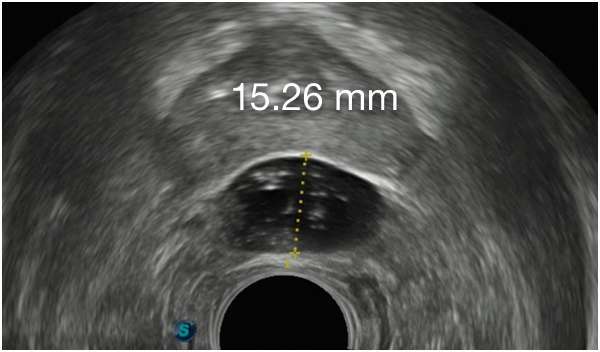

Implant Symmetry RESULTS6 >95%

Pivotal Trial Patients; % of implants centered on prostate midline

First Barrigel Cases - Consecutive Patients (Same Day)

TRUS images courtesy of Daniel R. Welchons, MD

Urologist; New York, United States

DR. WELCHONS’ INJECTION TECHNIQUE

IN RECTAL SPACING